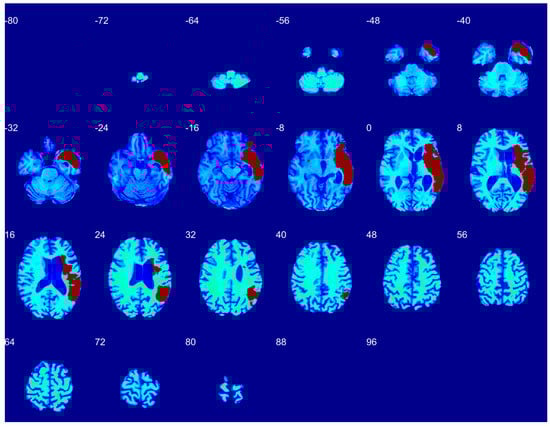

3.1. Qualitative Performance

3.2. Quantitative Performance